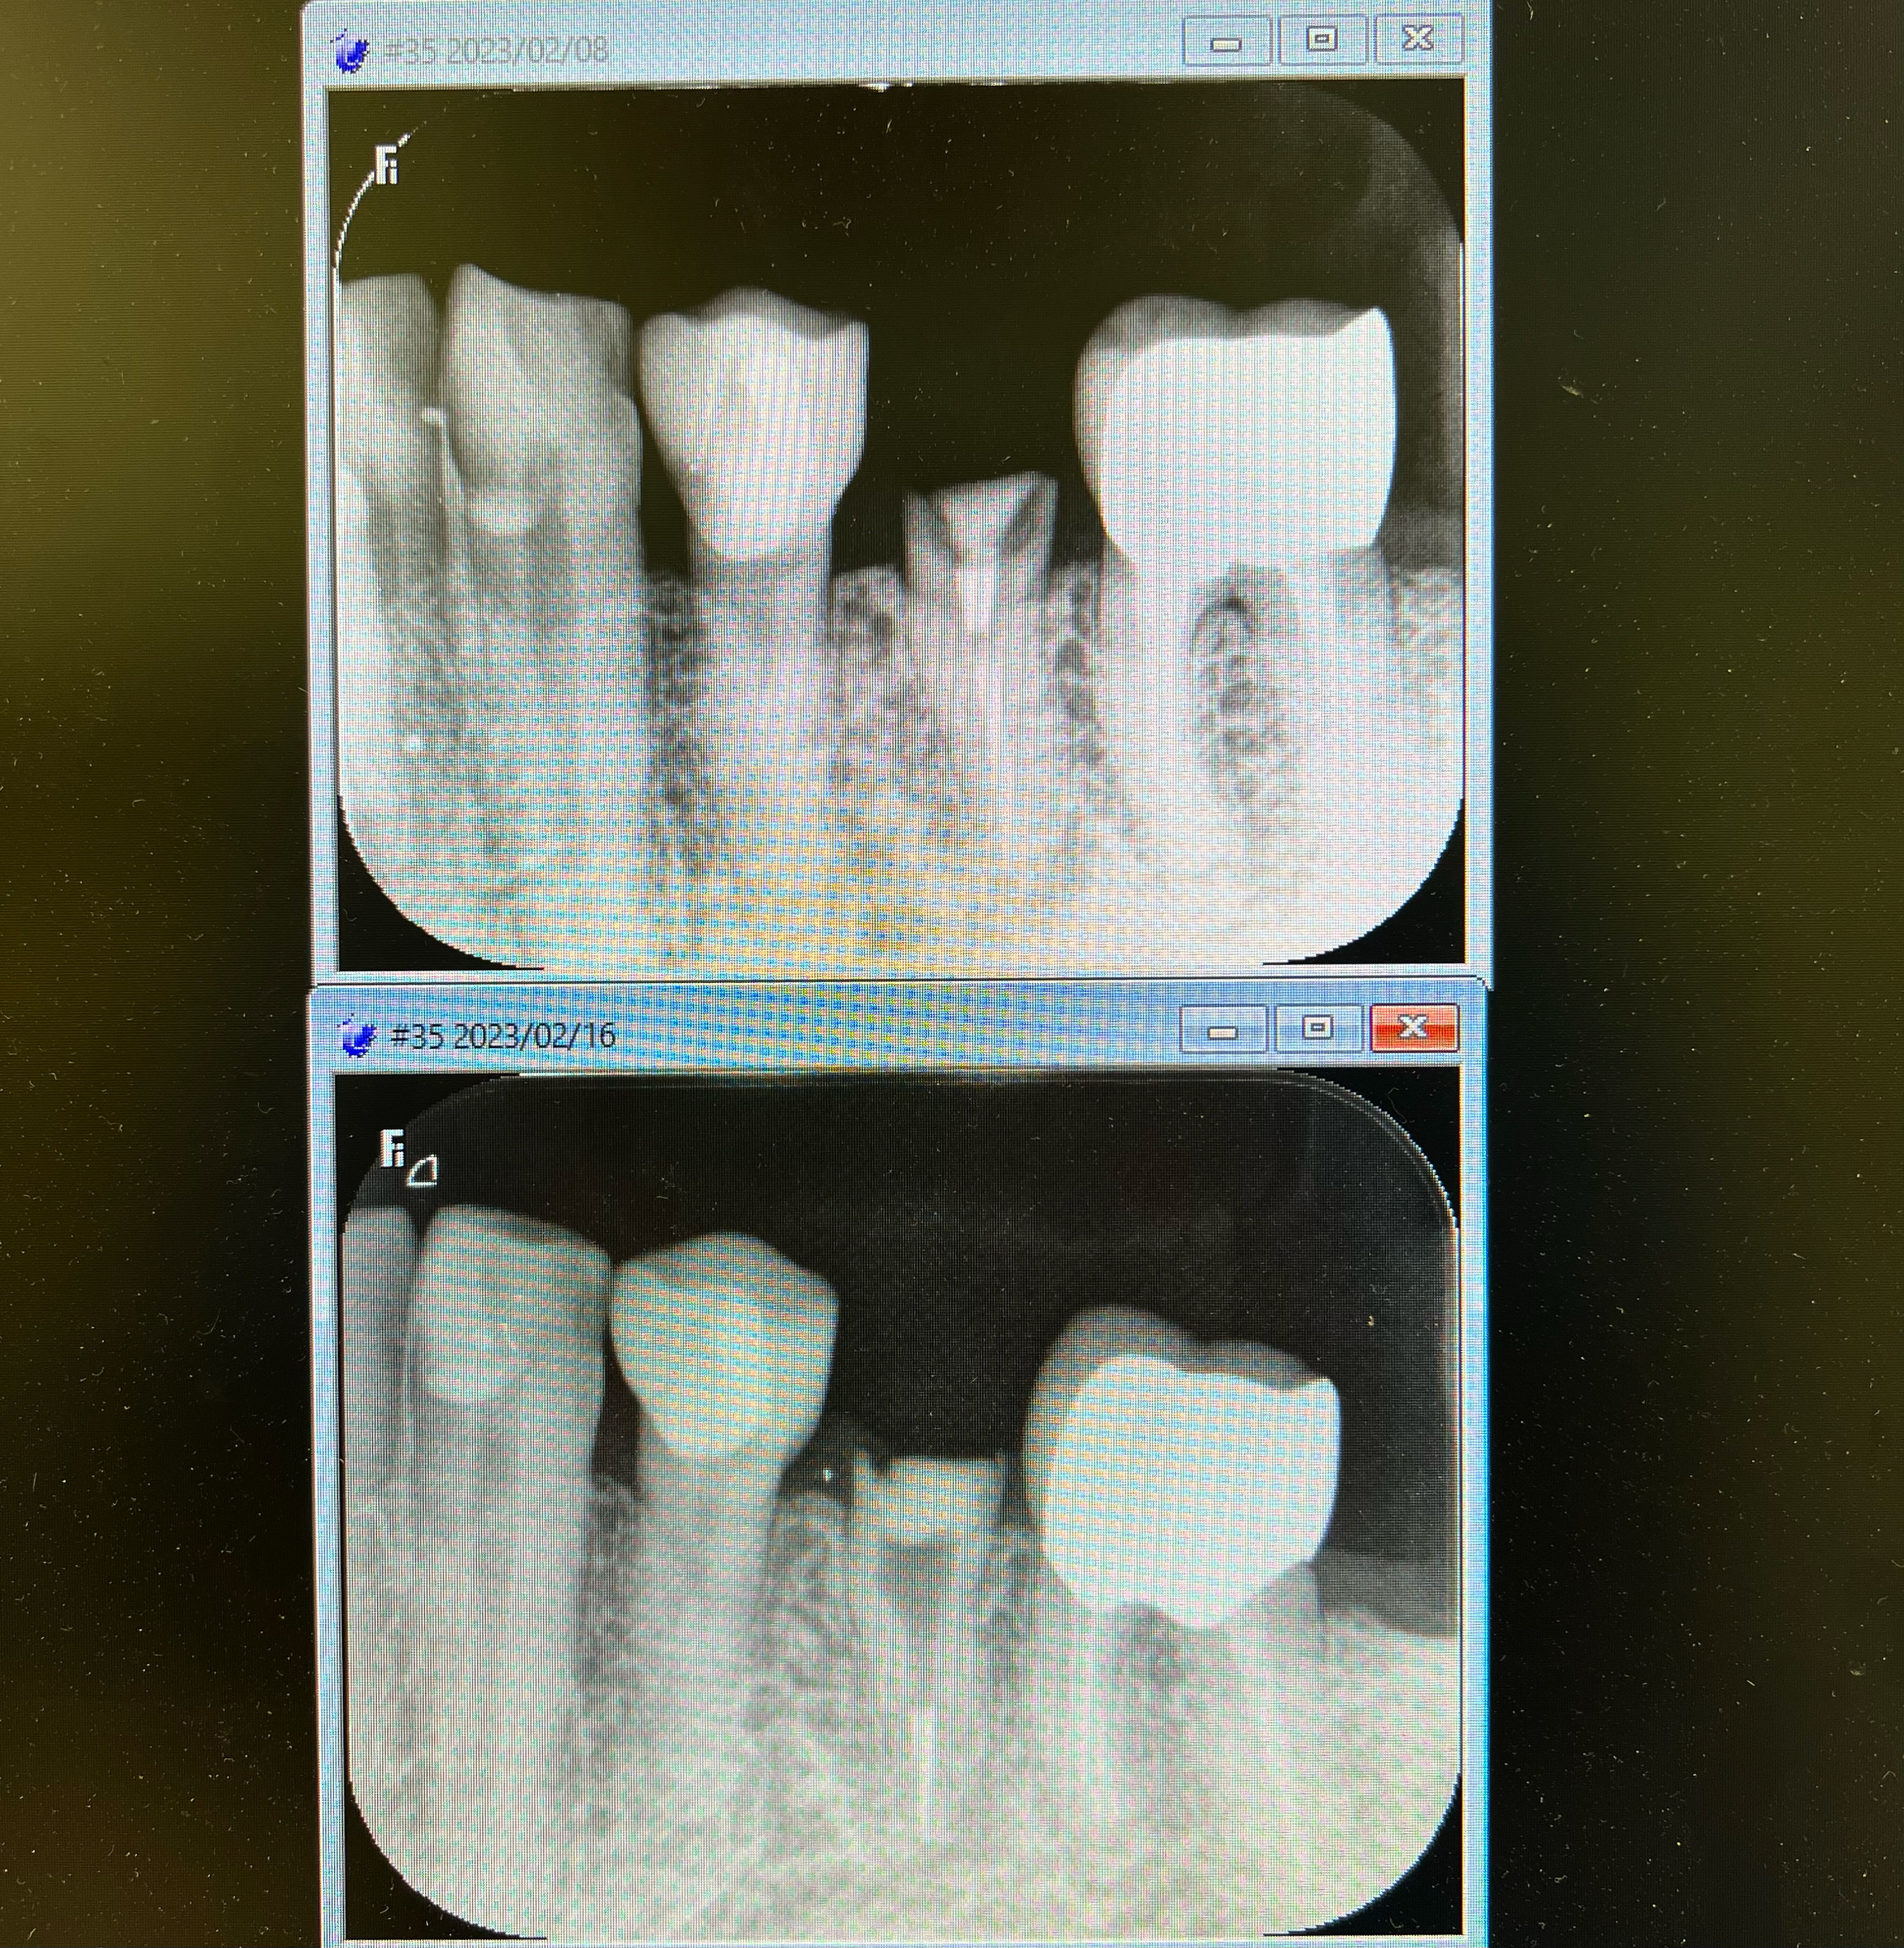

抜歯と言われた歯を残しました

2023/09/26症例